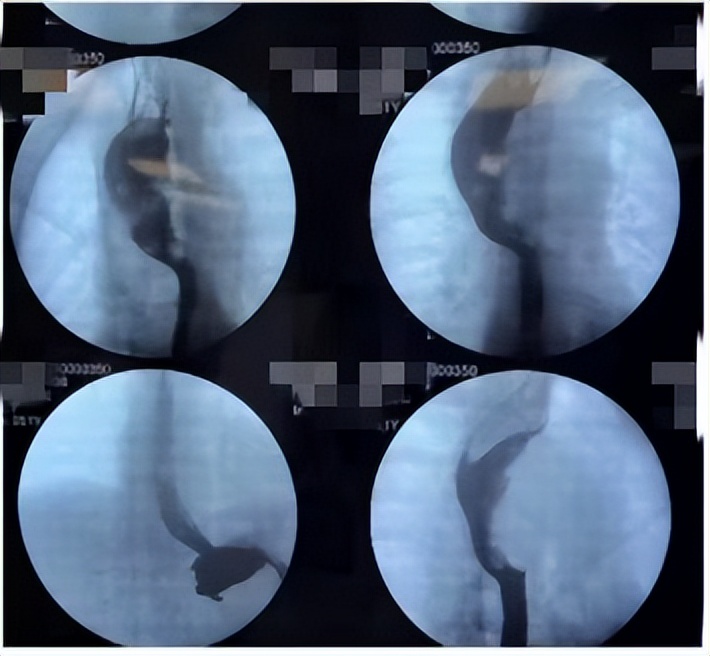

气管镜检查示:气管中下段管腔呈外压性狭窄(狭窄段长约8 cm),狭窄为60%~80%,镜身挤压过后可见隆突变钝。右主支气管、右中间支气管呈外压性狭窄,狭窄为20%~30%,黏膜充血肿胀。左主支气管通畅。

针对病灶来源、手术径路、手术方式、麻醉方式进行多学科会诊,最后术前诊断为后纵隔肿瘤,食管来源。拟行颈胸腹三切口全食管切除术。患者取左侧卧位,经右侧第4肋间进胸;翻身取平卧位,行管状胃食管吻合。麻醉选择快速序贯诱导插双腔管(插双腔管的目的是为了支撑隆突附近的气道),有条件者,在插双腔管之前,可镇静下置入喉罩,并借助支气管镜评估气道。